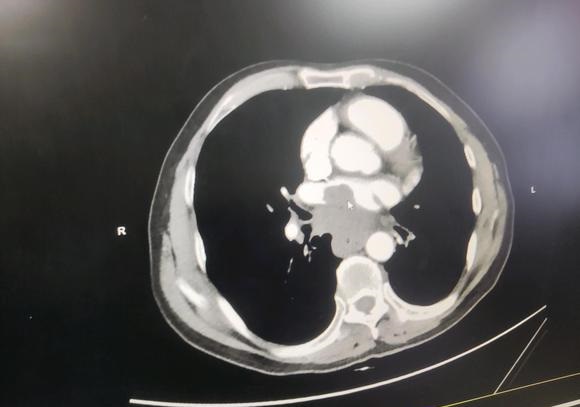

这种是扩散没有

懂的老铁,能帮忙看看吗?这个单子什么意思?病情进展到哪一步了?